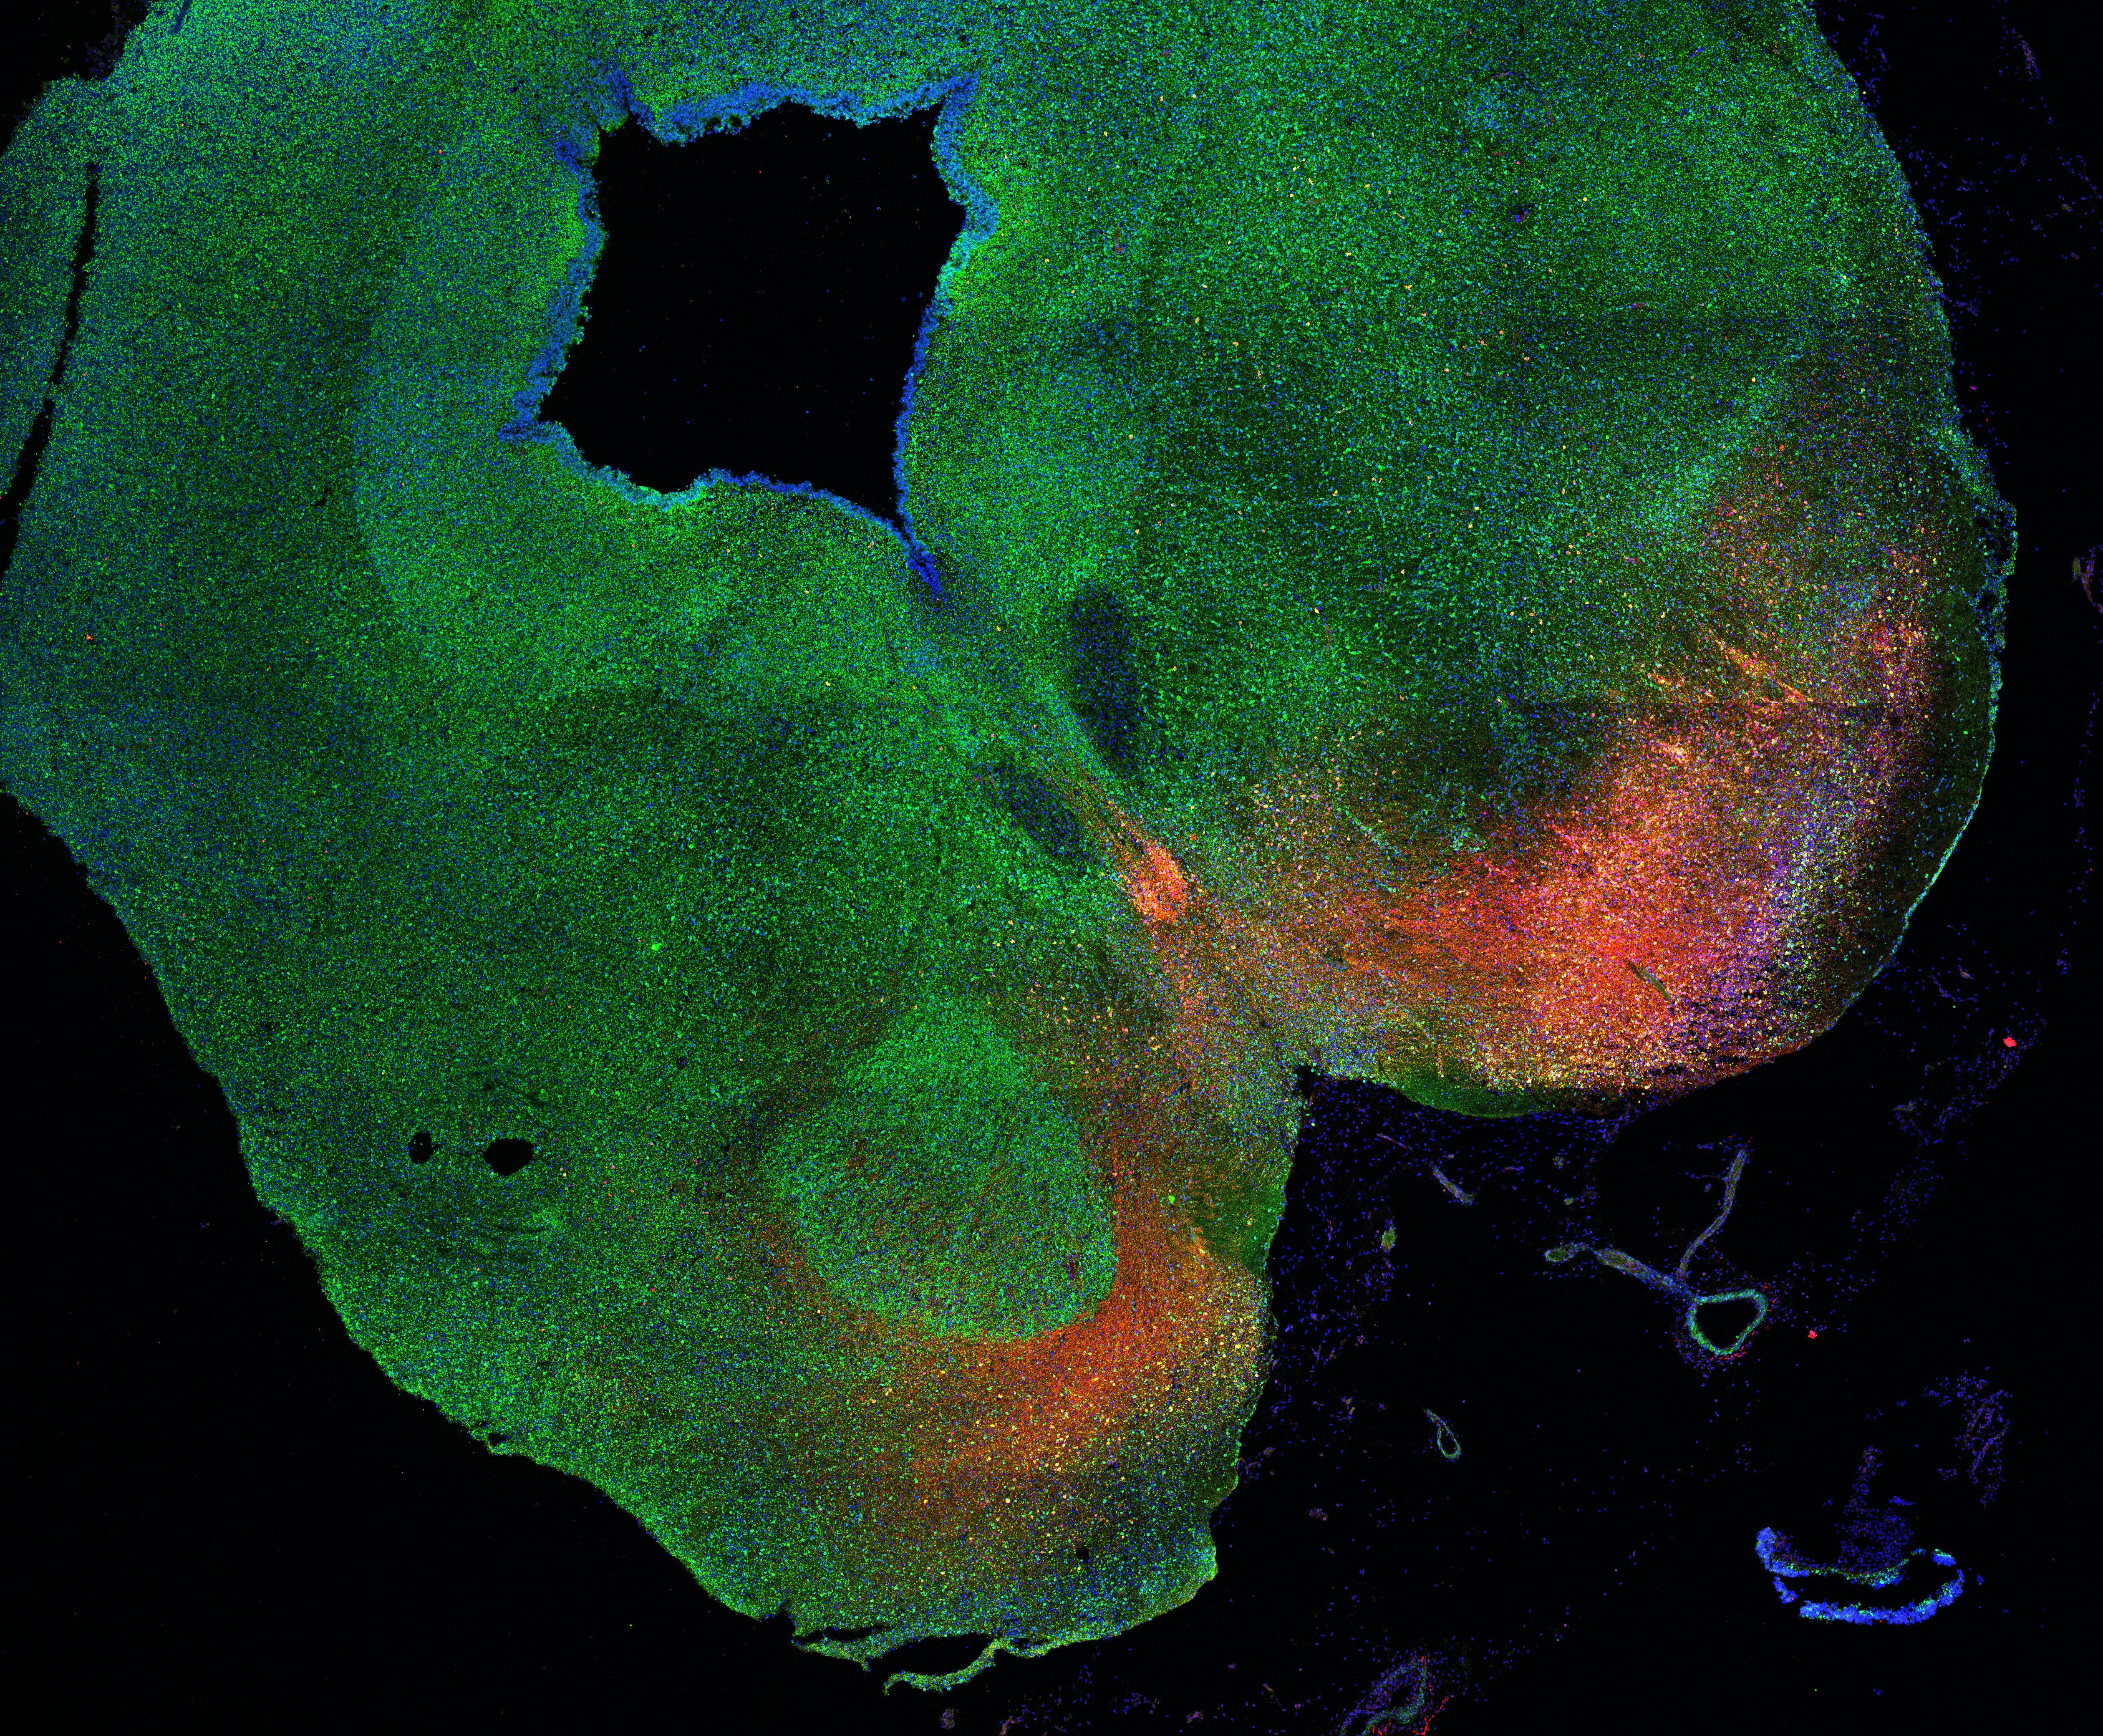

An anatomical analysis of the developing human midbrain from 6 post-conceptional weeks (PCW) to 22 PCW reveals increased tissue complexity, characterized by the emergence of dopaminergic nuclei, as highlighted by immunofluorescence analysis for tyrosine hydroxylase (TH).

Merged

6PCW human midbrain

7PCW human midbrain

11PCW human midbrain

13PCW human midbrain

15PCW human midbrain

17PCW human midbrain

19PCW human midbrain

22PCW human midbrain